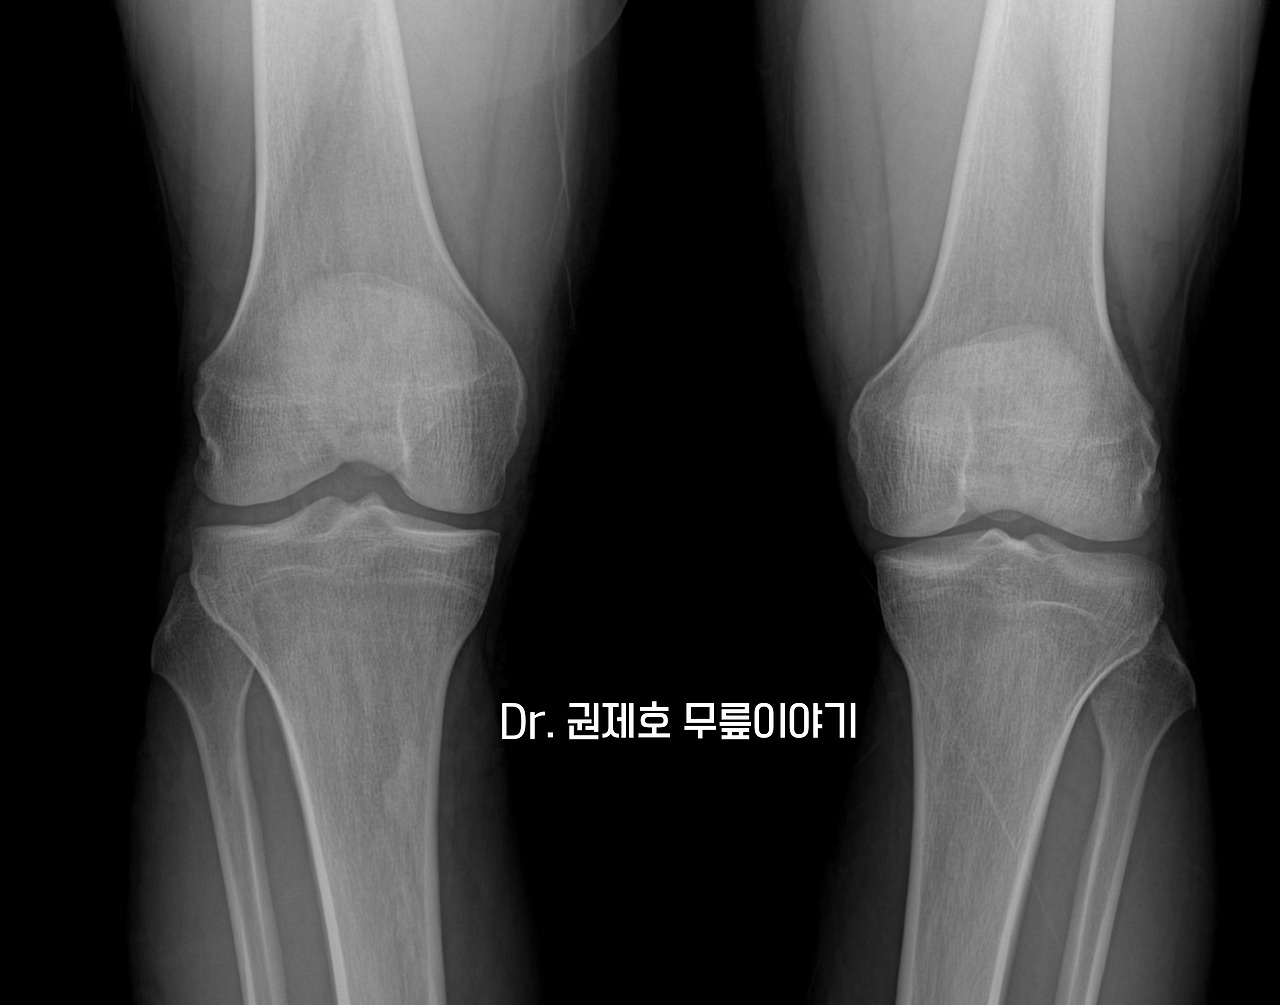

무릎연골판 방사형파열 (12).jpg

사진을 찍어보니 젊은 사람이어서 그런지 정상이다.